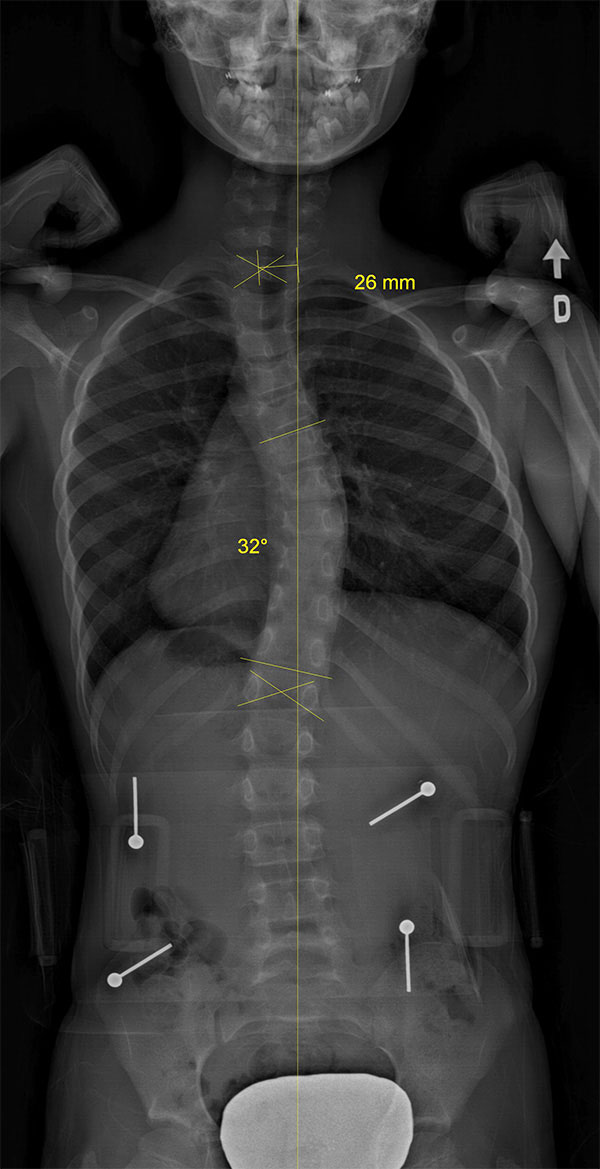

Étude de cas d’une autre adolescente avec une scoliose

Le cas d'une adolescente âgée de 12 ans et 9 mois (Risser 0) au début du traitement.

Cette jeune fille, dont la photographie montre une difformité importante du dos, souffre d’une scoliose déjà sévère dont la courbe atteint 42° (angle de Cobb) au début du traitement.

Dès l'installation du SpineCor®, on note une réduction de la courbure grâce à l'action dynamique des bandes élastiques malgré une scoliose très importante.

Après 30 mois de traitement, la scoliose est stabilisée à 33° et la croissance terminée. Il est normal avec une courbure d'amplitude aussi marquée de remarquer une légère perte de correction par rapport au premier jour du traitement, car la colonne vertébrale de la patiente a continué de grandir durant le traitement et la courbe d'évoluer. Quand on débute plus jeune le traitement sur des scolioses de moindre amplitude, il est souvent possible d'éviter ces phases d'aggravation.

Mais au final, la dernière photographie prise après le sevrage du traitement montre clairement que la posture de la jeune fille présente un aspect beaucoup plus normal et symétrique qu'au début. Grâce à SpineCor®, l'esthétique de son dos s'en trouve améliorée encore plus que la correction réelle de sa courbe, ce qui aura inévitablement un effet positif direct sur son image de soi.